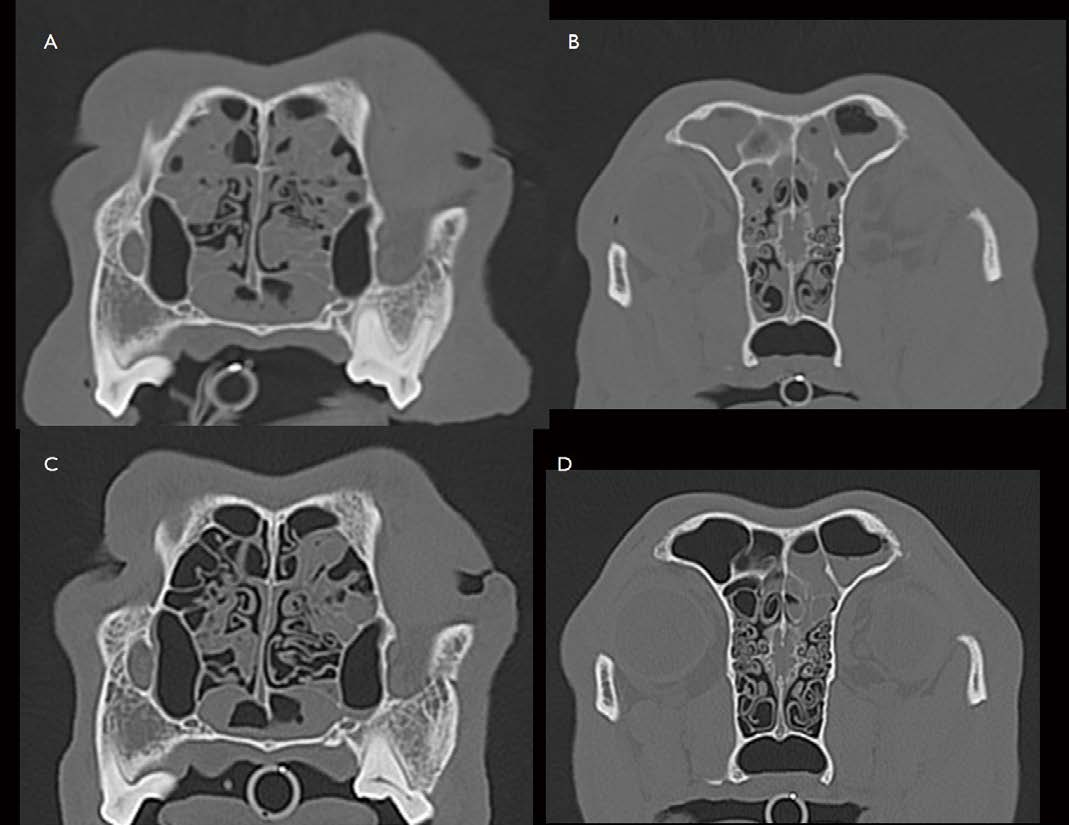

[대한수의사회지 5.png

9살의 수컷 33kg의 mongrel이 6개월 이상 nasal discharge, sneezing을 보여 내원하였습니다. Plain X-ray에서 양쪽 비강의 미약한 밀도 상승 소견이 관찰되었고, CT 검사에서 양쪽 비강 및 부비동 내 삼출물 축적 및 점막 비후가 관찰됩니다(그림 5. A, B). 유의적 수준의 종괴 및 비강을 둘러싼 large bones 및 nasal septum의 destruction은 관찰되지 않습니다. 부비동의 hyperostosis 관찰됩니다. 이 환자는 rhinoscopy, biopsy, 배양 검사로 이물, 폴립, 종양, 감염원을 배제하고 idiopathic lymphocytic plasmacytic rhinosinusitis로 진단할 수 있었습니다. 내과적 관리로 6개월 뒤 CT 재평가하였을 때(그림 5. C, D) 비강 및 부비동의 점막 비후, 삼출물 축적 소견은 어느 정도 개선되어 관찰됩니다. Idiopathic rhinosinusitis는 Plain X-ray 검사에서 주로 양측성 비강 내 밀도 상승 소견을 보입니다. CT 검사에서도 주로 양측성으로 비강 내 삼출물 축적, 점막 비후 소견이 관찰되고, 만성적으로 심할 경우 nasal turbinate destruction이 관찰됩니다. 또한 frontal sinus의 밀도 상승 및 벽의 hyperostosis가 관찰됩니다. 종양과는 달리 비강을 둘러싸는 Large bones의 destruction은 잘 관찰되지 않습니다.